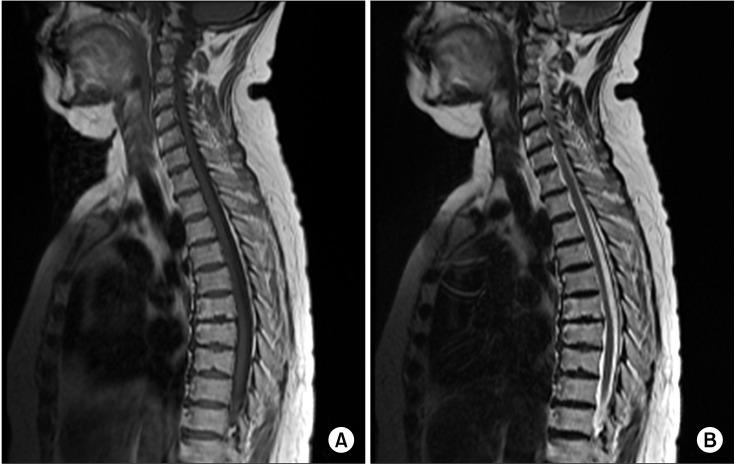

During the early stage of postherpetic neuralgia, an epidural block on the affected segment is helpful in controlling pain and preventing progression to a chronic state. The main neurologic complication following an epidural block is cord compression symptom due to an epidural hematoma. When neurologic complications arise from an epidural block for the treatment of postherpetic neuralgia, it is important to determine whether the complications are due to the procedure or due to the herpes zoster itself. We report a case of a patient who was diagnosed with herpes zoster myelitis during treatment for postherpetic neuralgia. The patient complained of motor weakness in the lower extremities after receiving a thoracic epidural block six times. Although initially, we believed that the complications were due to the epidural block, it was ultimately determined to be from the herpes zoster myelitis.

在带状疱疹后神经痛的早期,受累节段的硬膜外阻滞有助于控制疼痛和防止进展为慢性状态。硬膜外阻滞后主要的神经系统并发症是由于硬膜外血肿导致的脊髓压迫症状。当硬膜外阻滞治疗带状疱疹后神经痛出现神经系统并发症时,重要的是要确定并发症是由于该操作还是由于带状疱疹本身引起。我们报告了 1 例在治疗带状疱疹后神经痛时被诊断为带状疱疹性脊髓炎的患者。该患者在接受 6 次胸椎硬膜外阻滞治疗后出现下肢运动无力。虽然最初我们认为并发症是由于硬膜外阻滞引起的,但最终确定是由带状疱疹性脊髓炎引起的。